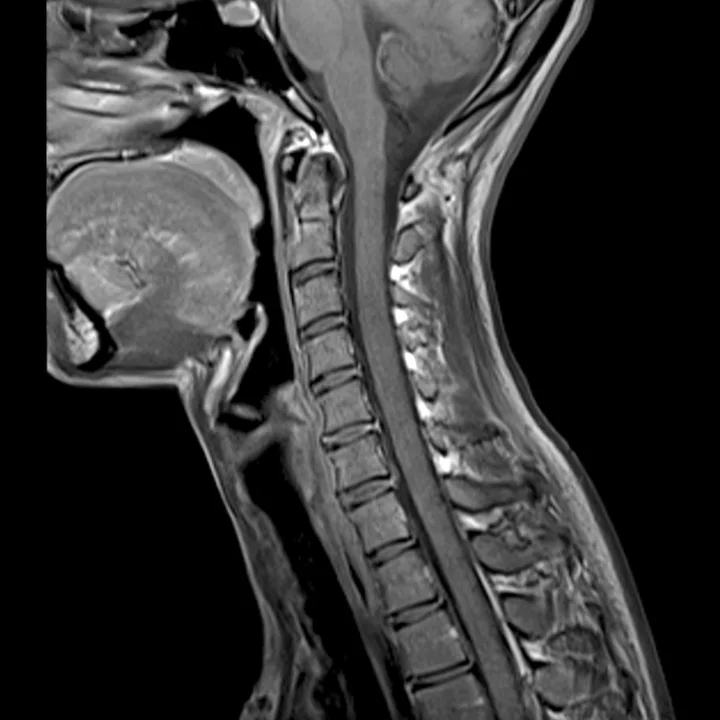

MRI Disc Herniation from Car Crash.jpeg

Disc Herniation Injury from a Car Crash.